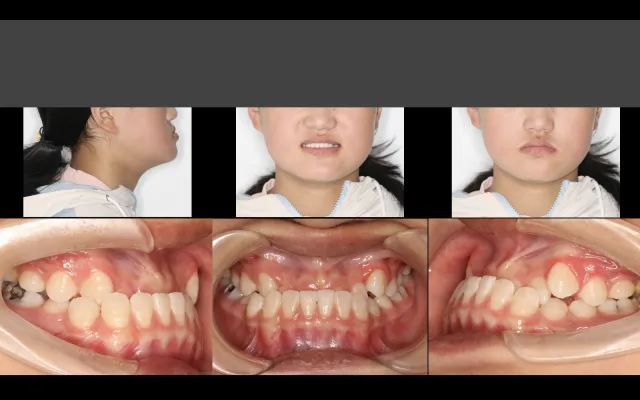

突面畸形的矫治策略

1.轻度突面畸形的矫治策略

2.牙性突面畸形的矫治策略

3.骨性突面畸形的矫治策略

4.突面畸形的颌平面控制,如何实现“逆旋”

5.从突面畸形到“侧颜杀”